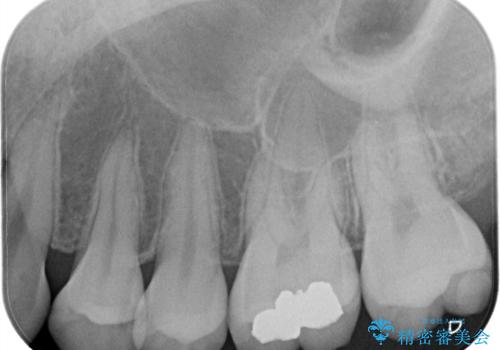

- 虫歯が神経まで達していたのですが、術前の検査と顕微鏡下で見た神経の状態からVPTの適応と判断し神経を残す治療をしました。

汚染されている神経は除去し残りの神経を残すためVPTを行いバイオセラミックのバイオシーシーラーで充填しオールセラミッククラウンで治療を行いました。治療後2年経過しましたが、神経は温存され経過は良好です。